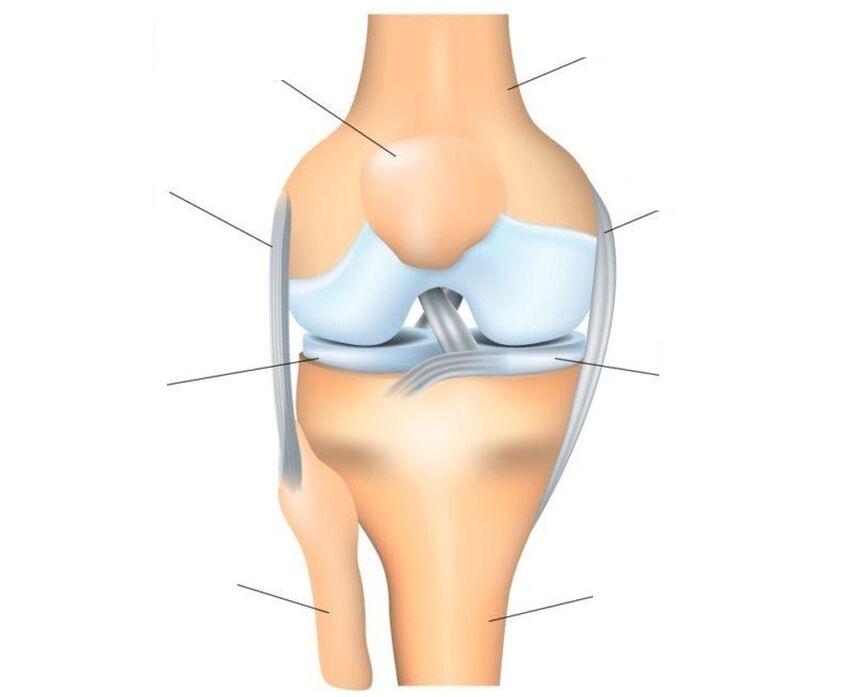

Das Kniegelenk ist das komplexeste Gelenk, da es die Hauptlast trägt. Struktur: Drei Knochen (Femur, Schienbein und Kniescheibe bilden ein einziges Trochleagelenk, bestehend aus zwei miteinander verbundenen Gelenken: femorotibial (tibiofemoral) und femoral-patellofemoral (patellofemoral).

Die Patella ist ein flacher Sesambeinknochen (zusätzlich im Gelenk), der am Kopf des Femurs befestigt ist, in seiner konkaven Rille gleitet und als Block fungiert. Strukturmerkmale: Die vordere Oberfläche der Patella ist mit Periost bedeckt, die hintere Oberfläche, die mit dem Femur verbunden ist, ist mit hyalinem Knorpel bedeckt. Die Patella wird durch Bänder gestärkt: Haupt- und Seitenbänder – vertikal (oben und unten) und horizontal (seitlich – innen und außen).

O überträgt die Kraft des Musculus quadriceps femoris auf die Muskel-Skelett-Formationen des Unterschenkels und sorgt so für die Streckung des Unterschenkels am Kniegelenk. Die Oberfläche der gelenkbildenden Knochen ist mit Knorpel bedeckt, der als Stoßdämpfer fungiert. Zusätzliche Stoßdämpfer, die das Gelenk vor Verletzungen schützen, sind zwei halbmondförmige Knorpelmenisken, die sich zwischen Femur und Tibia befinden. Das Gelenk wird durch Bänder, Sehnen und die umgebende Kapsel in der richtigen Position gehalten.

Verletzungen und Erkrankungen betreffen verschiedene Gelenkgewebe. Nicht alle können krank werden. Knorpelgewebe besitzt somit keine Nervenenden und kann daher unmerklich und schmerzlos zerstört werden. Doch die Bänder und die Gelenkinnenhaut verfügen über viele Nervenenden und reagieren bei Verletzungen oder entzündlichen Prozessen sofort, was sich in starken Schmerzen äußert. Bei einer erheblichen Zerstörung des Gelenkknorpels können Schmerzen mit der Beteiligung des Periostes, der äußeren Knochenschicht mit guter Innervation, einhergehen.